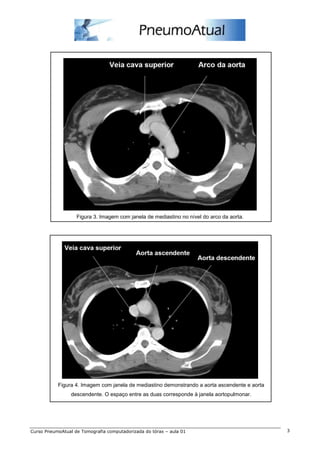

Figura 3. Imagem com janela de mediastino no nível do arco da aorta.

Figura 4. Imagem com janela de mediastino demonstrando a aorta ascendente e aorta

descendente. O espaço entre as duas corresponde à janela aortopulmonar.